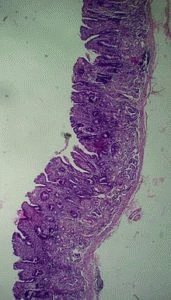

Атрофічний гіперпластичний гастрит вважається рідкісною формою хронічного захворювання ШКТ, сприяє збільшенню слизової оболонки. Захворювання поширюється в антральной частини шлунка. Якщо пізно звернутися за допомогою до лікаря, збільшується ризик появи онкологічної хвороби.

Зазвичай хворому складно звернути увагу на ознаку, здатний сказати про наявність атрофічного гастриту, симптом не буває явно вираженим. Згаданий вид хвороби вимагає негайної допомоги лікарів. Хвороба вважається досить підступним і серйозним явищем, провокуючим серйозне витончення слизової шлункової стінки. Іноді з’являються виразки і шлункова кровотеча.